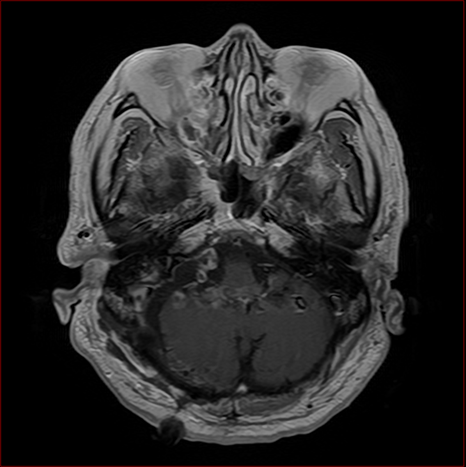

聴神経腫瘍ー術後